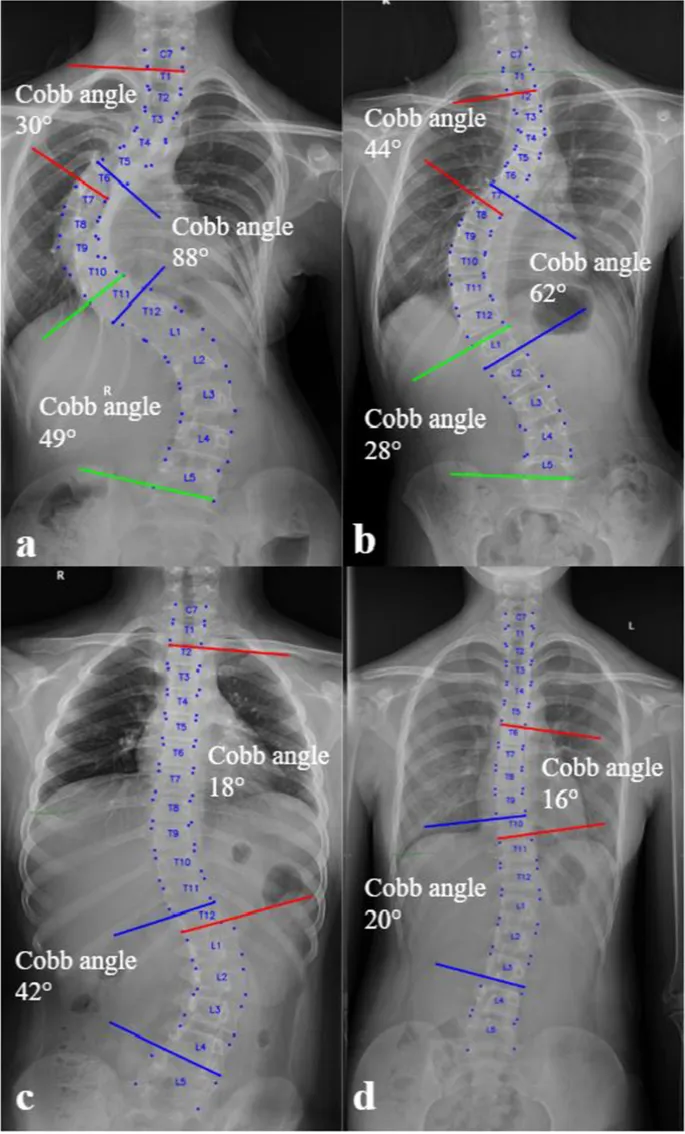

Definition: Lateral spinal curvature >10° (Cobb angle), often with vertebral rotation.

- Cobb Angle: $Cobb Angle = \alpha + \beta$ (angle between endplates of most tilted vertebrae).

- X-ray (Full Spine AP/Lat): Curve magnitude, pattern, flexibility.